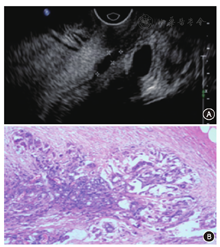

2.不同位置直肠癌的超声诊断结果与病理结果对照(表2)。低、中位直肠癌超声诊断的kappa值分别为0.27,0.63,高位直肠癌因例数太少无法统计kappa值,其准确率为100%。直肠腔内超声诊断对于中高位直肠癌的一致性较好,而低位的一致性差,而且出现T分期低估的比例较高达33.3%。超声诊断比照病理结果,出现低估和高估的图像(图1,图2)。

本研究中出现不同程度分期过高或过低,其中以低估较多(21例,24.4%),与文献不同[12]。回顾图像发现21例低估患者中,均为小病灶,范围在1~2 cm,可能由于病灶较小,加上新辅助治疗后,局部组织间质纤维化、组织变性,直肠壁结构紊乱,影响超声对病灶的结构分辨力[13](图1)。高估7例(8.1%,7/86),回顾图像发现,可能与病灶部位的病理改变有关,病理变化多提示为重度放疗反应,在镜下呈黏液湖、大量炎性细胞浸润(图2),超声图像中肠壁黏膜层增厚、肌层与直肠系膜分界不清,误以为是肿瘤浸润。